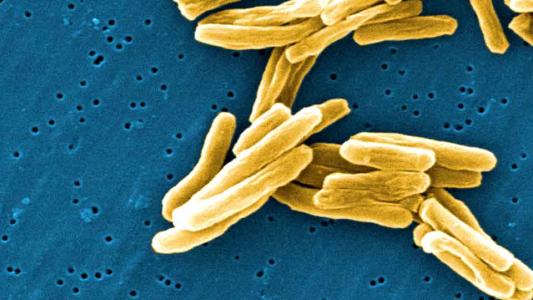

Two billion people have TB. What should we do about it?

In the fight against TB, sometimes it's better to just get along.